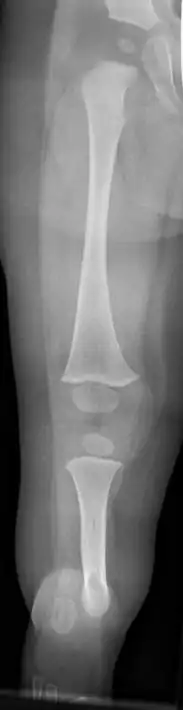

![]() | |

| Fibula Hemimelia in patient affecting right side | |